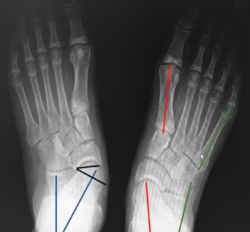

Pie en serpentina (skewfoot)

El pie en serpentina o en Z constituye una deformidad rara en el pie, que combina valgo del retropié con aducción del antepié (Figura 18).

Figura 18. Pies en serpentina. A: radiografía dorsoplantar de la deformidad en serpentina; B: imágenes radiológicas postoperatorias inmediatas, donde se aprecia osteotomía de Mosca y técnica de Cahuzac percutánea; C y D: imagen clínica y radiológica un año tras la intervención.

A menudo infradiagnosticado, suele presentarse como un metatarso aducto resistente al tratamiento. En la radiografía se manifiesta con signos de valgo del retropié con divergencia AC aumentada y aducción del antepié al nivel de la articulación de Lisfranc.

En caso de indicación quirúrgica se debe corregir el doble componente de la Z con osteotomía de alargamiento de la columna externa (para corregir el valgo) más corrección del antepié mediante técnica de Cahuzac (apertura de la cápsula C1M y osteotomía de los metatarsianos centrales) modificada en percutánea(20).